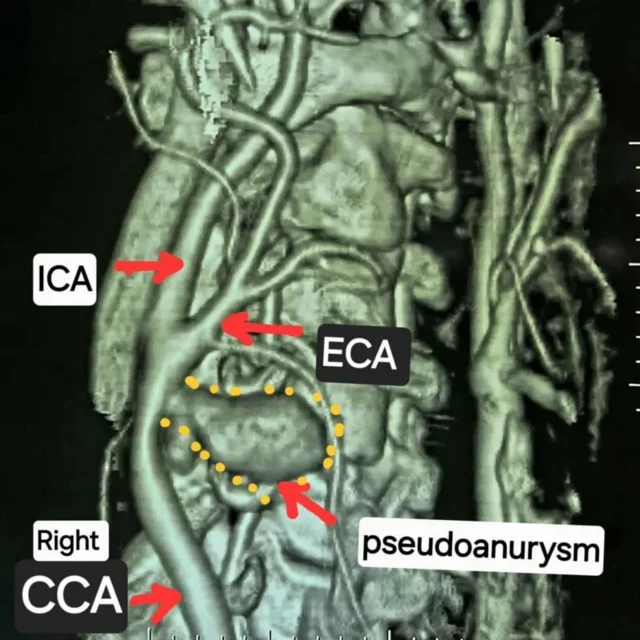

طبی معائنے سے پتہ چلا کہ راہل کی دائیں کیروٹڈ شریان پھٹ گئی تھی۔

گردن میں دائیں اور بائیں جانب موجود شریانیں انسانی دل سے دماغ تک خون لے جاتی ہیں۔

راہول کی گردن میں دائیں کیروٹڈ شریان پھٹ جانے کی وجہ سے گردن تیزی سے خون سے بھر گئی اور شریان کے گرد خون بھرنے کی وجہ سے غبارے جیسا ڈھانچہ بن گیا جسے طبی زبان میں pseudoaneurysm کہتے ہیں۔